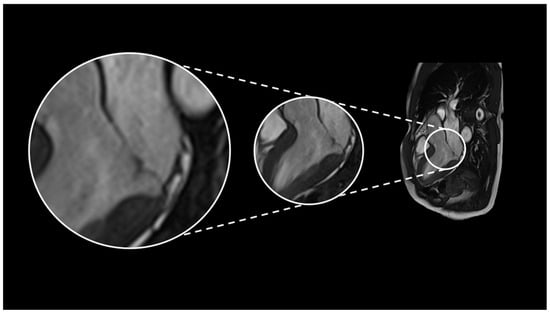

1. Introduction and Definition

2. Case Series